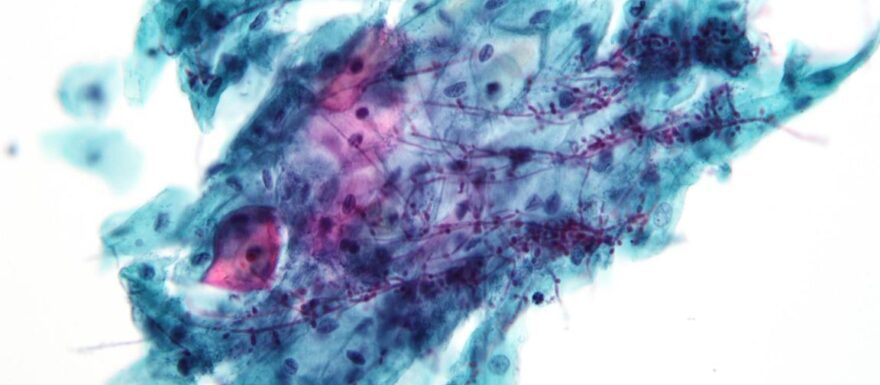

Deze nascholing gaat in op de mogelijke oorzaken van fluorvaginalisklachten, die uiteenlopen van onschuldige variatie tot infecties, waaronder seksueel overdraagbare aandoeningen (soa’s). In Blok A staat de diagnostiek centraal, waaronder gynaecologisch onderzoek en laboratoriumonderzoek van fluor. Ook de afweging wanneer wel of niet te behandelen komt aan bod.

• weet je hoe de diagnostiek van fluorvaginalisklachten verloopt

• ken je de verschillende oorzaken bij de verschillende afwijkingen